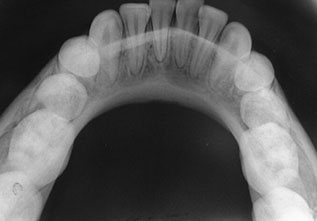

OCCLUSAL VIEW

Occlusal X-rays show the roof or floor of the mouth and are used to find extra teeth, teeth that have not yet erupted through the gums, jaw fractures, a cleft palate, cysts, abscesses or growths. Occlusal X-rays may also be used to find the position of any foreign object accidently entrapped into upper & lower jaws.